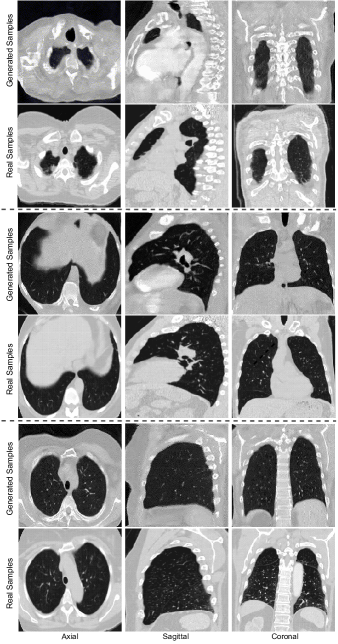

Appendix 0.A Sample Synthetic CT-scans from CT-SGAN

The evaluation of the generated CT-scans was designed to be done under two scrutinies: (1) qualitative inspection of the generated volumes from CT-SGAN where the diverse variation and consistency across all three views of axial, coronal, and sagittal were met (2) quantitative demonstration that synthetic data from CT-SGAN are valuable to build deep learning models for which limited training data are available. We evaluate the efficacy of data augmentation by three nodule detection classifier experiments (i) training with only real dataset (ii) training with only 10,000 synthetic volumes (iii) training with 10,000 synthetic volumes as a pretraining step and then continue to train on the real dataset (i.e., fine-tuning).

The visual qualitative evaluation of the generated volumes was studied based on three criteria: (1) Anatomical consistency of the generated slices, (2) Fidelity of generated slices to the real ones, and (3) diverse generation of CT-scans. Regarding the first two, Figure 1 shows these requirements were met as in thousand of generated CT-scans we rarely noticed any anomalies. For the high quality of the slices and slabs, we observed consideration of 3D slices and the inclusion of both patient- and slice-specific noises played important roles. As to the diversity in the generated CT-scans, i.e. to avoid mode collapse, and also to ensure stability in training, the discriminators’ losses contained the gradient penalty discussed in [15] introducing variations in the generated volumes. While CT-SGAN was preferably trained with Wasserstein loss [1], we did not notice a drastic change when the vanilla Jensen-Shannon loss was employed. Also, even though artifacts could appear in the generated CT-scans, the presence of them was partially related to the noise in real CT-scans produced by scanners.